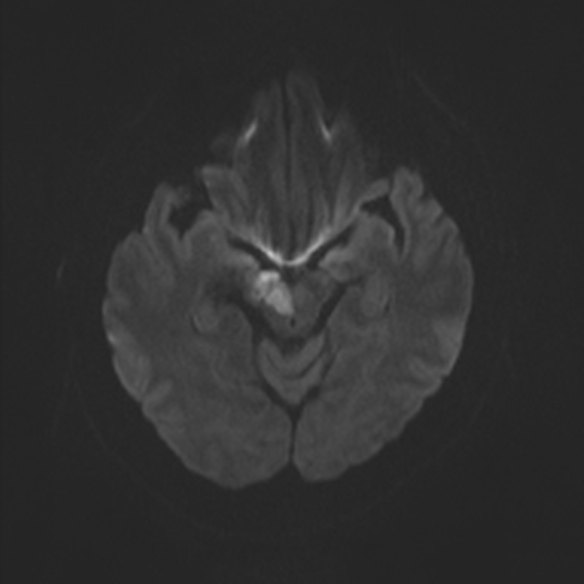

In this MRI image of the brain there is a region which has sufferd from and acute infarction/stroke. Can you recognize the region? if you can can , which are the structures (nuclei, pathways) that are most likely affected by the lesion and what could be the possible neurological outcomes in this patient ?

View this question